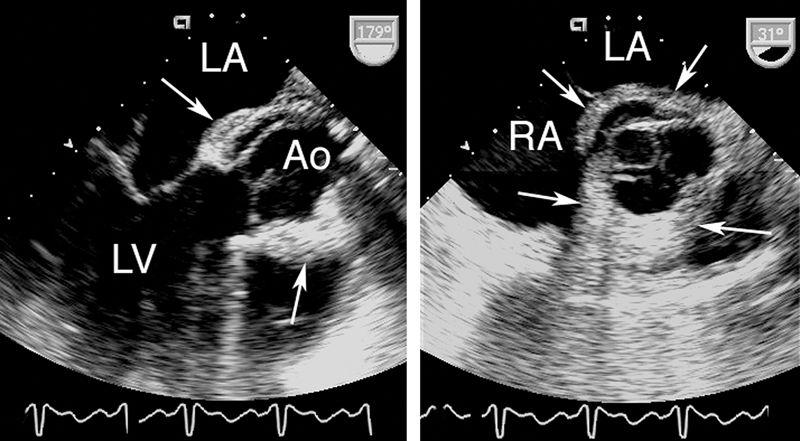

فحوصات تشخيصية لبعض امراض القلب والشرايين التاجية